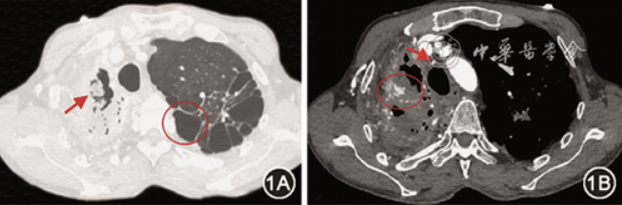

患者入院后仍有咯血,肺动静脉、支气管动脉CTA提示体动脉、肺动脉均受累,经充分评估病情后行“体动脉、肺动脉造影术+栓塞术”治疗。第一步:穿刺右侧股静脉置入8F血管鞘(TERUMO),运用5F PIG导管行双肺动脉造影,造影提示右肺动脉主干增宽,右肺动脉各肺段远端低灌注未见显影(图2A);第二步:穿刺右侧股动脉置入5 F 血管鞘,根据CTA图像,使用C3、H1、MIK、RLG、SIMMONS 2、MPA(Cook medical)等各型导管行双侧支气管动脉,双侧锁骨下动脉,双侧膈下动脉、食管固有动脉、肋间动脉造影,可见1支右侧支肋共干、2支左右共干支气管动脉、右侧第2、4、5、6、7肋间动脉,右侧胸廓内动脉、1支异位起源于右侧肋颈干的右侧支气管动脉、右侧肋颈干动脉、右侧胸上动脉、右侧胸外动脉、右侧肩胛下动脉、食管固有动脉异常,主干增粗、扭曲,末梢紊乱,并见明显体-肺动脉分流(图2B,2C),另可见右侧肺动脉A1、A3支远端呈瘤样扩张(图2D);第三步:沿股静脉入路使用MPA导管结合1.98 F微导管(Asahi)超选择性插管后右侧肺动脉A1、A3支远端瘤样扩张处,使用金属弹簧圈(Cook medical)栓塞,复造影,瘤样扩张消失;随沿股动脉入路使用300 μm聚乙烯醇颗粒(Cook medical)+500 μm明胶海绵颗粒(Varian)栓塞右侧支肋共干、左右共干支气管动脉、右侧第2、4、5、6、7肋间动脉、食管固有动脉;右侧锁骨下动脉严重扭曲,无法超选择其分支血管(包括:右侧胸廓内动脉、异位起源于右侧肋颈干的右侧支气管动脉、右侧肋颈干动脉、右侧胸上动脉、右侧胸外动脉、右侧肩胛下动脉);第四步:穿刺桡动脉,置入6 F 血管鞘(TERUMO),超选至右侧锁骨下动脉分支血管,栓塞后复造影,末梢血管消失(图3A,3B)。术中患者无明显不适,即拔管、撤鞘后,弹力绷带压迫止血,患者安全返回病房。术后患者有少许暗红色血凝块,伴发热,于术后第5天上诉症状消失。患者出院后继续口服伏立康唑200 mg(1次/12 h)抗真菌治疗。随访半年咯血未复发。

图2 选择性右肺动脉造影结果显示,右肺动脉主干增宽、低灌注,右肺动脉各肺段远端未见显影(图2A红色箭头);锁骨下动脉近端扭曲(图2B红色箭头),腋动脉迂曲增粗;胸外侧动脉迂曲增粗(图2C红色箭头),与右上肺动脉交通,体肺分流形成(图2C红圈);体动脉-右侧腋动脉造影可见肺动脉显影,提示肺动脉远端瘤样扩张(图2D红色箭头)